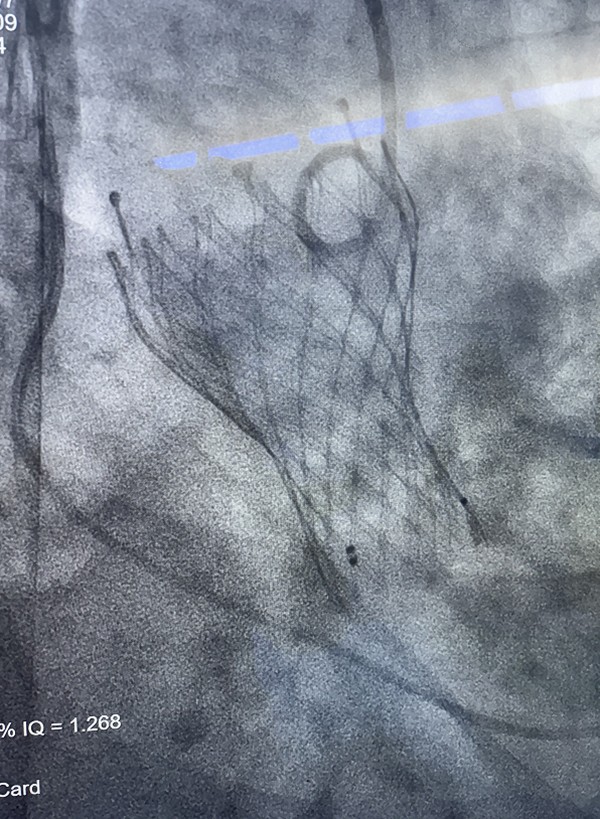

在谷长平教授指导下,麻醉与围术期医学科制定个性化麻醉方案。在全麻诱导前,麻醉医生李旺和万兴旺在局麻下建立了有创动脉测压通路,以便实时监测动脉血压,精准调控血流动力学状态。同时,他们在右侧颈内静脉植入双腔深静脉导管,用于中心静脉压监测和药物输注。在血管活性药物的支持下,患者平稳进入全麻状态。麻醉过程中,李旺和万兴旺精准调控麻醉药物剂量,确保患者在手术全程处于安全稳定的麻醉状态,同时最大限度地减少对心脏功能的负面影响。手术过程中,心内科副主任医师任金林为患者成功植入2枚心脏支架,有效改善了冠脉供血。随后,在副主任医师焦齐进行的体外循环辅助下,在王安彪主任指导下,主治医师董明亮和副主任医师李清宝共同完成手术。

顺利完成经皮主动脉瓣置换

术中瓣膜置换完成后,

术中实时经食道超声心动图监测